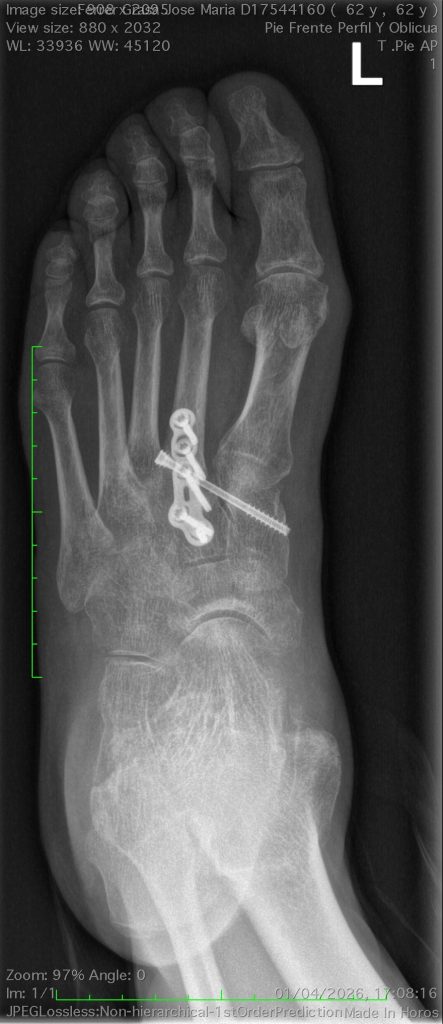

Para el diagnóstico es necesario realizar una radiografía con el fin de determinar la extensión de la juanete y cualquier artritis asociada.

En algunos casos, zapatos cómodos y anchos pueden ser suficientes para aliviar el dolor, así como plantillas y ortesis. Pero es muy importante para el tratamiento tener en cuenta cualquier anomalía en la biomecánica. Este término se refiere la postura del pie y de la pierna durante el movimiento, por lo que en algunos casos es necesaria la corrección quirúrgica.

Existen diferentes técnicas para la corrección quirúrgica, y esta se debe adaptar a cada caso de forma individual.

Dado que existen múltiples causas de metatarsalgia, la indicación quirúrgica y la técnica debe ser individualizada. Entre las intervenciones que se le pueden proponer están las osteotomías (cortes en los huesos para modificar su forma o su orientación) y las artrodesis o fusiones articulares, necesarias en algunos casos, cuando las articulaciones están desgastadas (artrósicas), para estabilizar una articulación con movilidad anormal o para corregir una deformidad. Para fijar estas osteotomías y artrodesis puede ser necesario el uso de implantes, placas y tornillos.